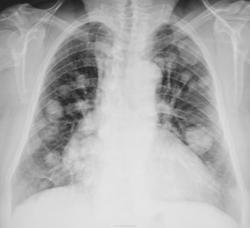

В обоих легких определяются множественные шаровидные образования однородной структуры, с четкими контурами, в диаметре, примерно: от 1,0 до 5,0 см. Предположительно mts рака почки.

В диф. ряд: атипичную форму многоликого саркоидоза.

Да, на сайте имеются подобные иллюстрации для саркоидоза.